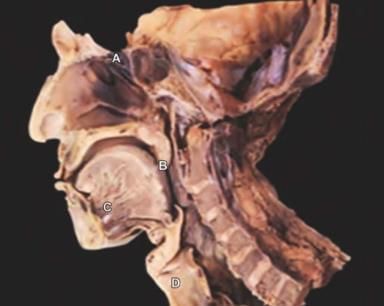

Patient undergoing surgery at the lateral part of skull. Postoperatively patient had aspirations without voice change. Nerve lesioned is: (AIIMS Nov 2019)

A patient was admitted with skull base trauma and difficulty in swallowing. The doctor was touching the marked structure. Which of the following cranial nerve is being tested? (NEET-PG 2021)

A patient with a fracture skull base at the temporo-occipital region, presented with difficulty in speaking post trauma. During investigation which structure should be tested which helps in diagnosis related with the points marked below? (INI-CET Nov 2021)

Third part of vertebral artery is related to which of the following marked region in the following diagram? (INI-CET Nov 2021)